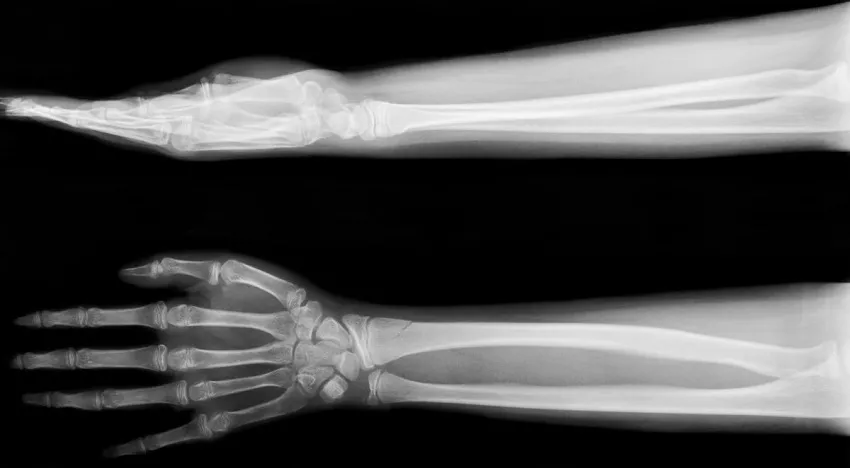

Рентген верхних конечностей

Рентген верхних конечностей позволяет определить, есть ли врожденные аномалии, дистрофия, перелом, вывих, растяжение или разрыв сухожилия, которые могут быть причиной боли в руке и ограничения подвижности. С его помощью также можно диагностировать различные заболевания — артроз, артрит, некроз плечевых головок, тендинит и другие. Кроме того, рентген кистей проводится, чтобы определить костный возраст детей и подростков. Сравнение полученных данных со специальными таблицами помогает выявить замедление либо ускорение их физического и полового развития, которое может быть следствием некоторых заболеваний.

Рентген верхних конечностей предполагает диагностику скелета, начиная от плечевого пояса (рентген акромиально-ключичного сочленения, ключицы и лопатки) до кончиков пальцев (рентген кисти, локтевого и лучезапястного сустава, локтевой и лучевой кости).